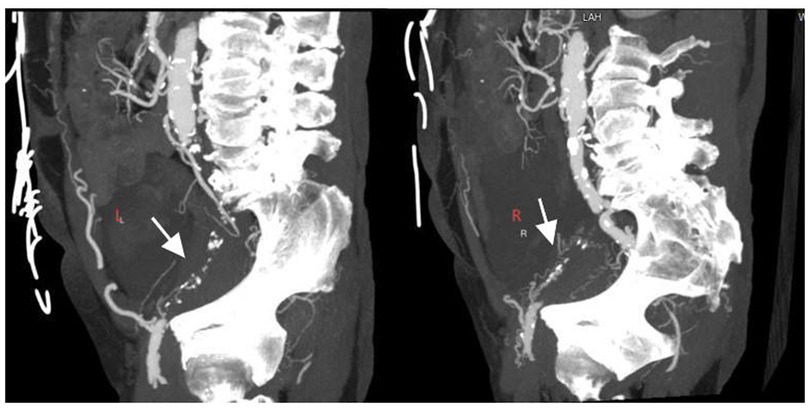

Figure 1

CT scan images of the abdomen showing two slices. Both images highlight spinal structures and blood vessels. White arrows point to specific areas, labeled as \

Figure 1. CTA revealing bilateral external iliac artery occlusion (white arrows).

A 74-year-old male was admitted to the hospital due to intermittent chest tightness lasting for 4 years, which had worsened over the past month. The patient has a history of hypertension for more than 10 years. Physical examination of the heart and lungs reveals no abnormalities. On 21 January 2025, coronary angiography performed at an outside hospital revealed 70%–80% stenosis of the left main terminal segment, 60%–70% stenosis in the proximal-to-mid left anterior descending artery (LAD), 99% ostial stenosis of the left circumflex artery (LCX), and complete mid-to-distal occlusion of the right coronary artery (RCA). Echocardiography showed left-ventricular segmental wall-motion abnormalities with an ejection fraction of 40%. Upper-extremity color Doppler ultrasound was normal, whereas lower-extremity computed tomography angiography (CTA) demonstrated bilateral external iliac artery occlusion (Figure 1). Diagnosis: Coronary atherosclerotic heart disease, unstable angina, NYHA functional class II, bilateral external iliac artery occlusion. The patient's coronary artery disease is complex, and the access route for interventional therapy is restricted. Coronary artery bypass grafting is recommended, but the patient refuses. Our treatment plan is to first address the occluded RCA and then schedule the treatment of the non-occluded LCA at a later date. This is because the RCA serves as the recipient vessel, while the LCA acts as the donor vessel providing collateral circulation to the RCA. This approach can reduce the intraoperative risks for the patient.